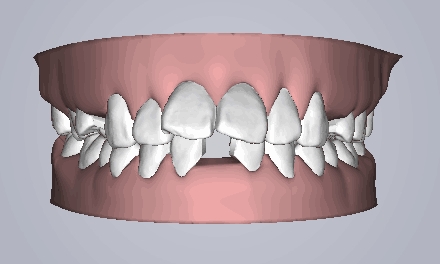

治疗方案动画

治疗预计效果和实际效果